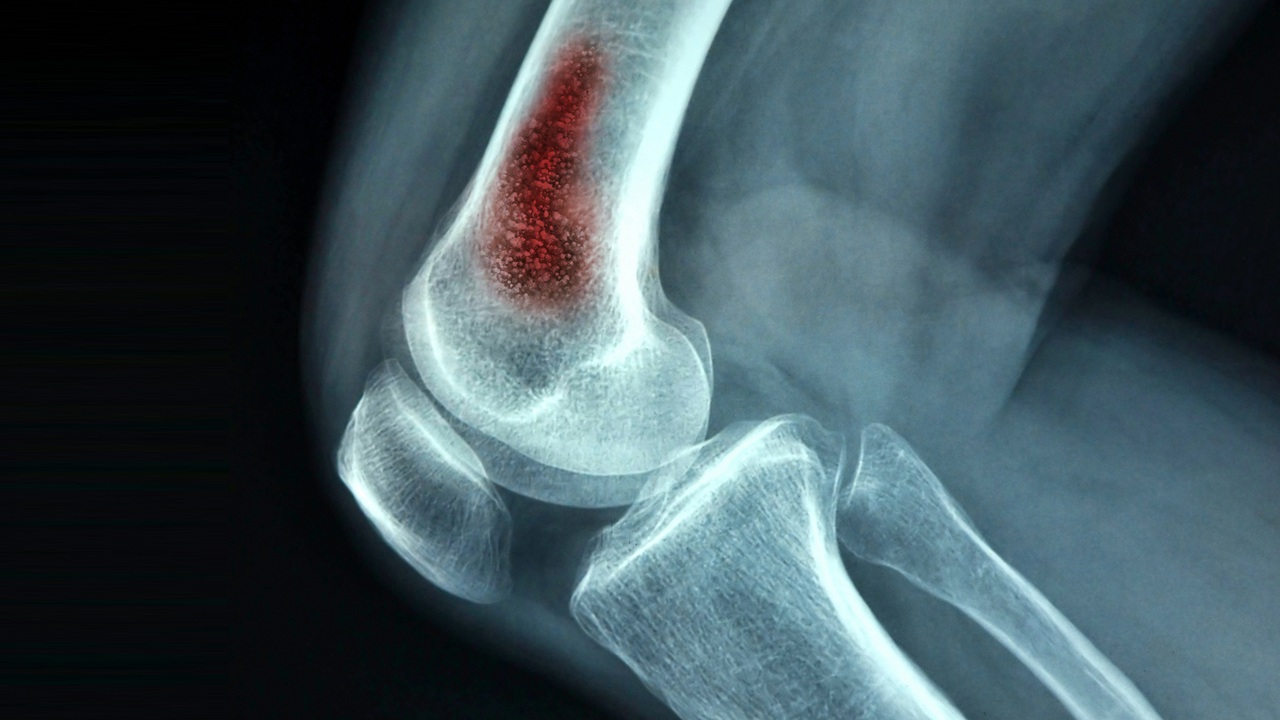

Osteomyelitis refers to an inflammatory bone disease mainly caused by an infection. The osteomyelitis market is witnessing significant growth due to various factors driving demand and innovation in treatments. The increase in the incidence of osteomyelitis, fueled by a rise in the prevalence of conditions that compromise the immune system, such as diabetes and peripheral arterial disease, acts as a primary market driver. This is coupled with the growing aging population, which is more susceptible to chronic conditions, including infections like osteomyelitis, thereby broadening the patient demographic. Advances in diagnostic technologies have also contributed to the market's expansion, enabling early detection and more effective management of the condition.